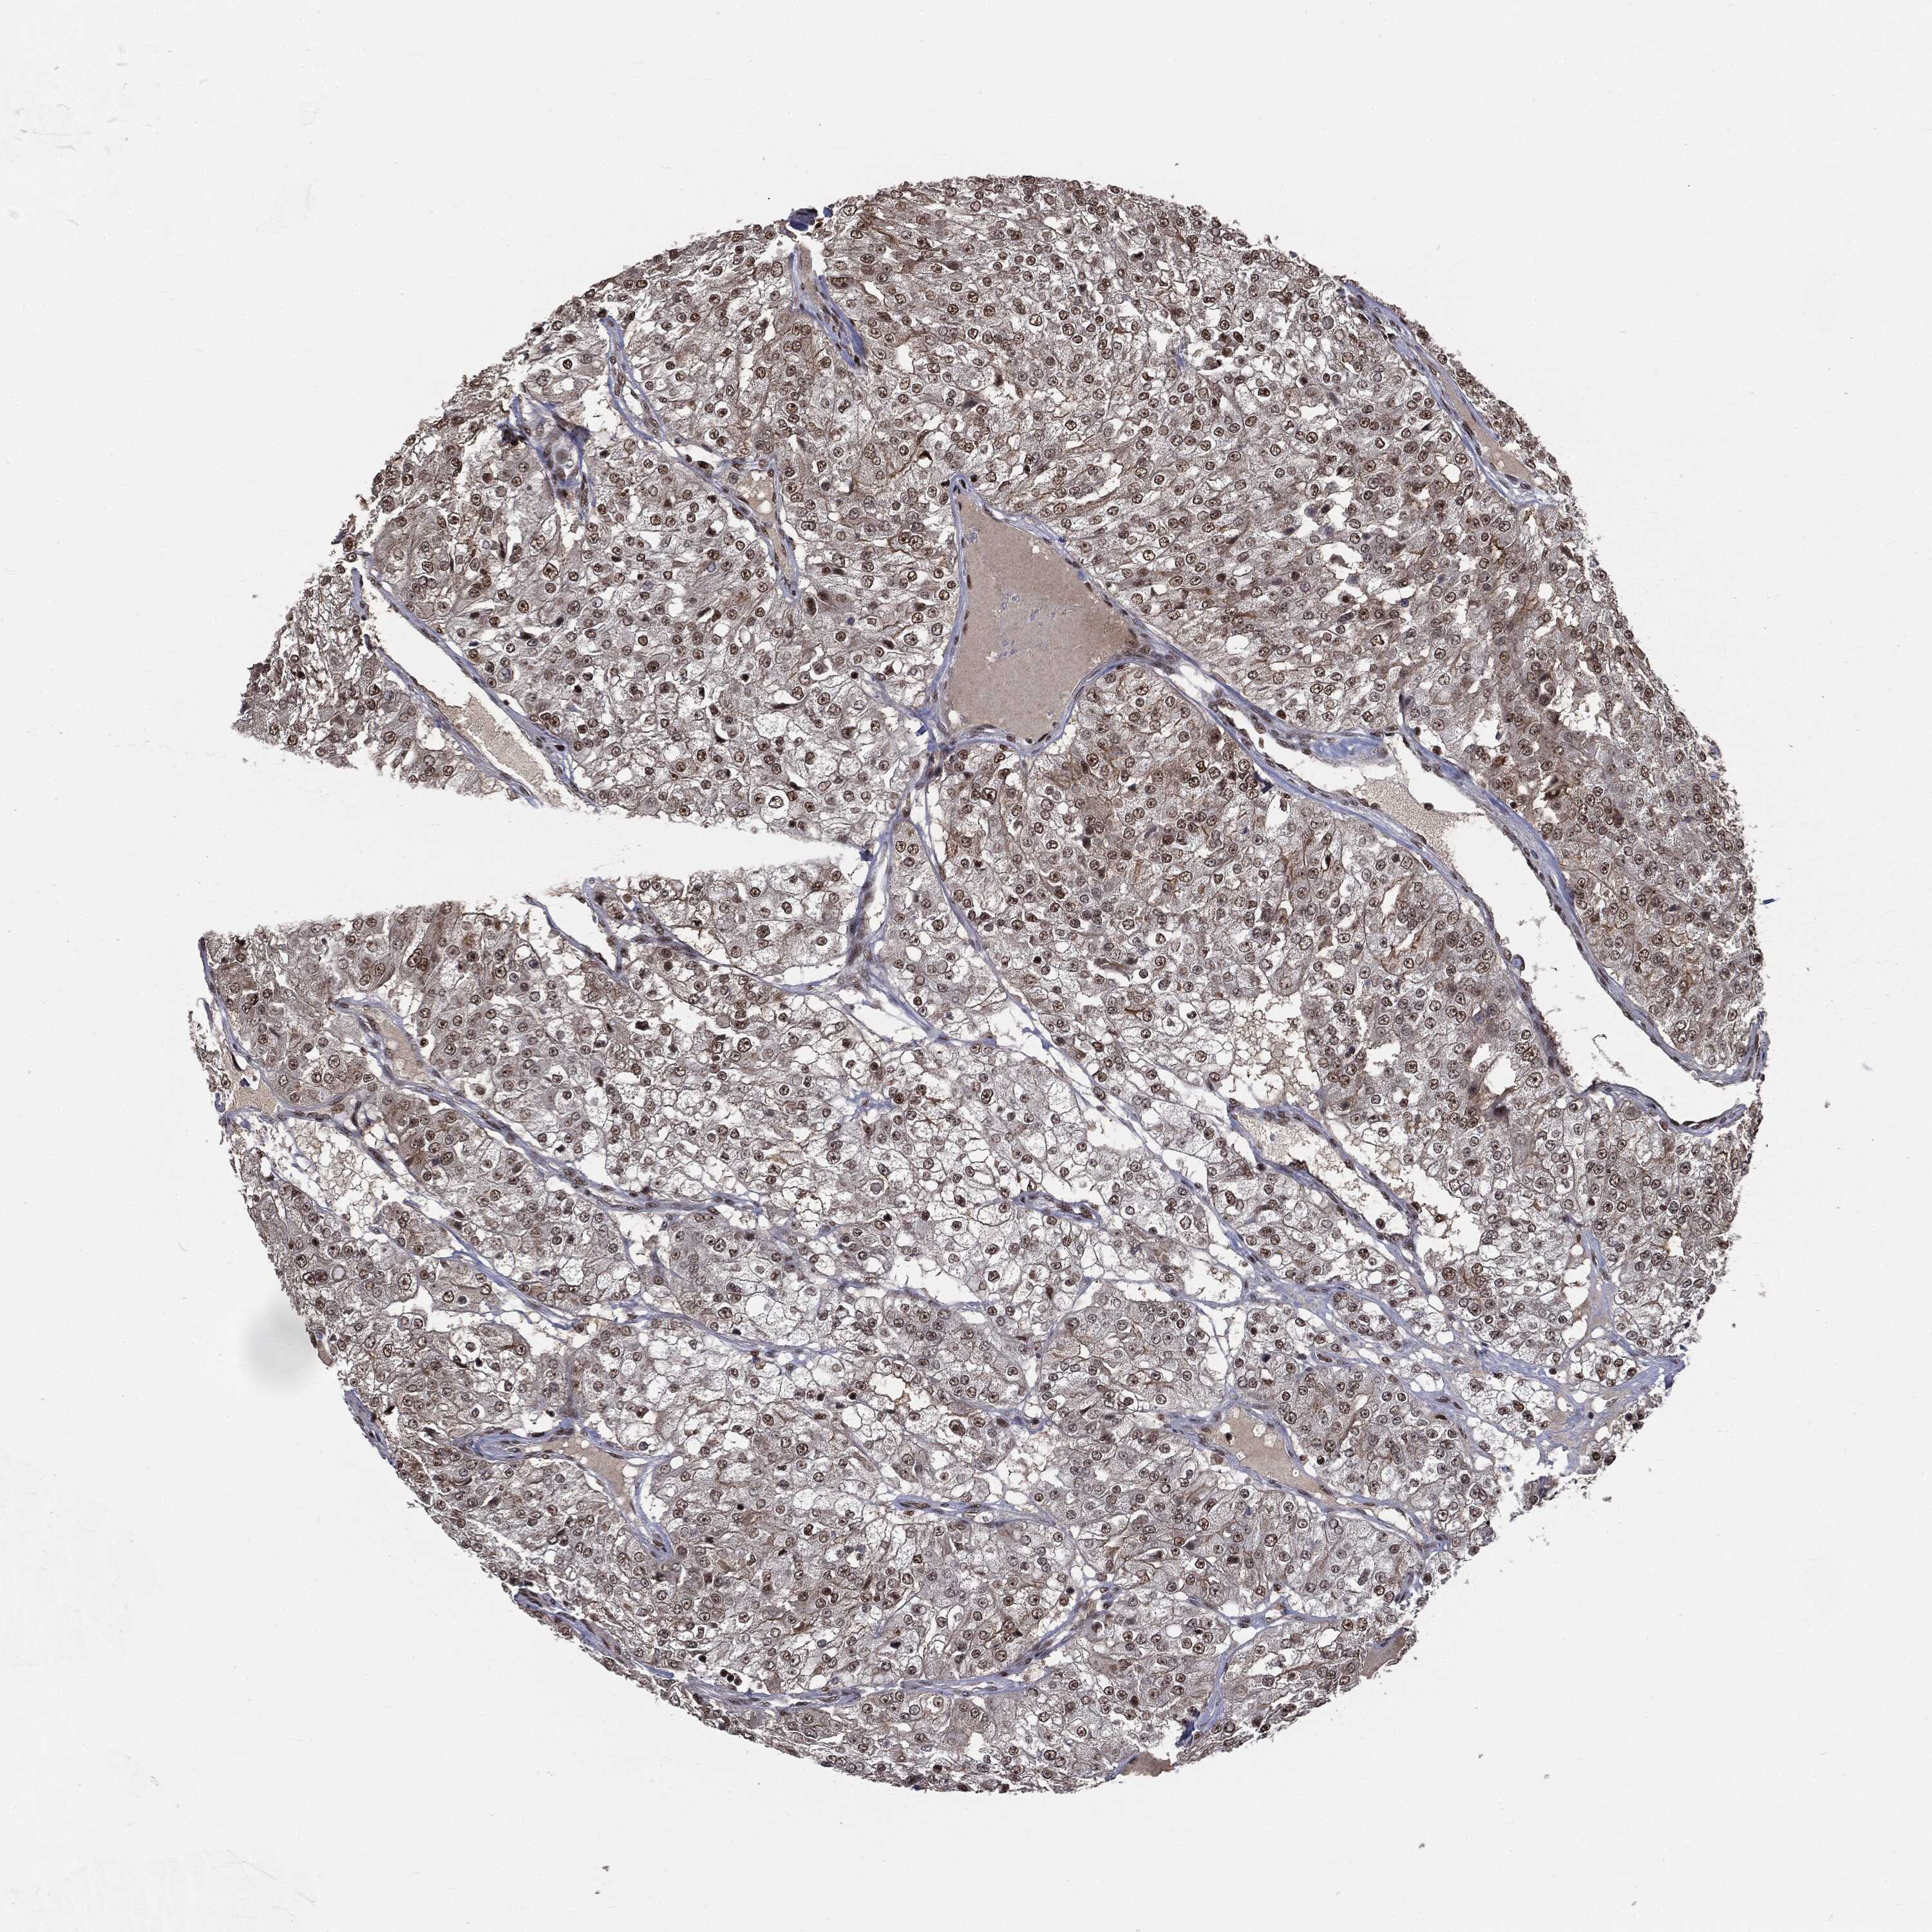

KIDNEY RENAL CLEAR CELL CARCINOMA (TCGA) - Interactive survival scatter ploti

The Survival Scatter plot shows the clinical status (i.e. dead or alive) for all individuals in the patient cohort, based on the same data that underlies the corresponding Kaplan-Meier plots. Patients that are alive at last time for follow-up are shown in blue and patients who have died during the study are shown in red.

The x-axis shows the expression levels (FPKM) of the investigated gene in the tumor tissue at the time of diagnosis. The y-axis shows the follow-up time after diagnosis (years). Both axes are complimented with kernel density curves demonstrating the data density over the axes. The top density plot shows the expression levels (FPKM) distribution among dead (red) and alive patients (blue). The right density plot shows the data density of the survived years of dead patients with high and low expression levels respectively, stratified using the cutoff indicated by the vertical dashed line through the Survival Scatter plot. This cutoff is automatically defined based on the FPKM cutoff that minimizes the p-score. The cutoff can be changed by dragging the vertical line or by entering a cutoff value in the square labeled "Current cut-off".

Under the Survival Scatter plot the p-score landscape (black curve; left axis) is shown together with dead median separation (red curve; right axis). Dead median separation is the difference in median mRNA expression between patients who have died with high and low expression, respectively. It is calculated as follows: median FPKM expression of dead patients with high expression - median FPKM expression of dead patients with low expression. This is intended to aid the user in visually exploring custom cutoffs and the associated p-scores and dead median separation.

Individual patient data is displayed and can be filtered by clicking on one or more of the category buttons on the top of the page. Categories describing expression level and patient information include: high, low, alive, dead, female, male and tumor stages. The scale of the x-axis can be toggled between linear and log-scale by clicking on the "x log" button. Mouse-over function shows TCGA ID, patient information and mRNA expression (FPKM) for each patient.

& Survival analysisi

Kaplan-Meier plots summarize results from analysis of correlation between mRNA expression level and patient survival. Patients were divided based on level of expression into one of the two groups "low" (under cut off) or "high" (over cut off). X-axis shows time for survival (years) and y-axis shows the probability of survival, where 1.0 corresponds to 100 percent.

DPH2 is not prognostic in Kidney Renal Clear Cell Carcinoma (TCGA)

Best expression cut offi

Based on the FPKM value of each gene, patients were classified into two groups and association between prognosis (survival) and gene expression (FPKM) was examined. The best expression cut-off refers the FPKM value that yields maximal difference with regard to survival between the two groups at the lowest log-rank P-value. Best expression cut-off was selected based on survival analysis .

When clicking on this number, the vertical dashed line indicating cut-off, the interactive survival plot, and the Kaplan-Meier curve will be adjusted to show results based on the best expression cut-off.

: 5.7

TCGA RNA samplesi

RNA-seq data is reported as average FPKM (number Fragments Per Kilobase of exon per Million reads), generated by the The Cancer Genome Atlas (TCGA) .

Normal distribution across the dataset is visualized with box plots, shown as median and 25th and 75th percentiles. Points are displayed as outliers if they are above or below 1.5 times the interquartile range. FPKM values of the individual samples are presented next to the box plot.

Average pTPM 8.2

Number of samples 521